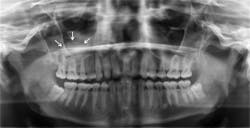

Radiographic distinguishing characteristics: The classic antral pseudocyst presents as a dome-shaped lesion on the maxillary sinus floor. Most have a very faint, opaque appearance on a radiograph. The lesion is usually well delineated (see Figure 1). There is sometimes confusion with the AP and polyps. Polyps are irregular in shape when compared to the AP. The fluid in polyps is in the loose connective tissue of the lamina propria of the lining of the sinonasal tract, and the mucosa is thickened by edema.